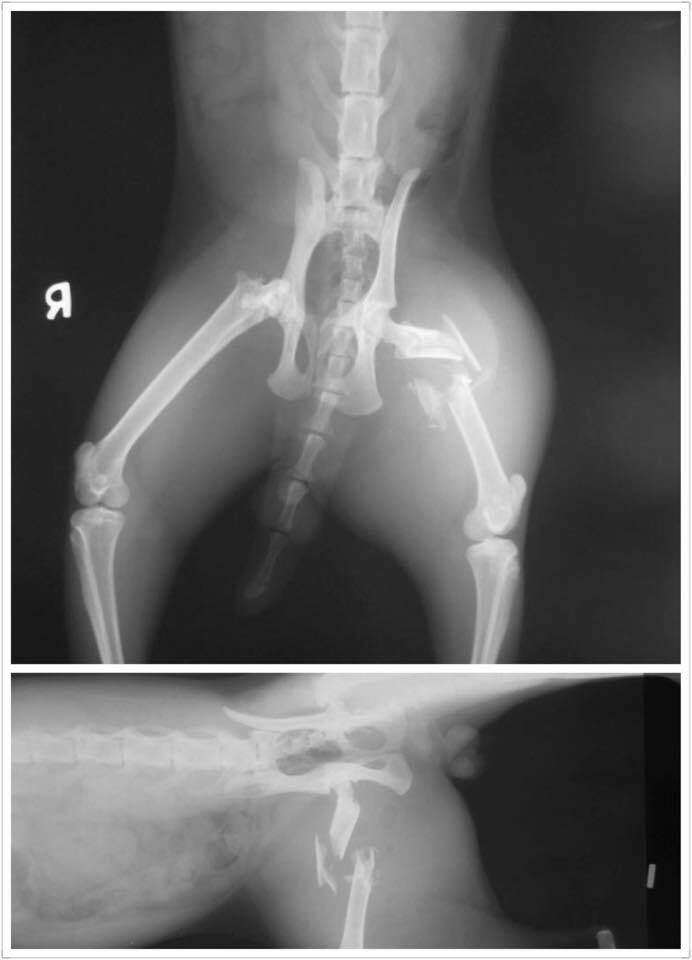

樂生動物醫院判定

左後腳股骨粉碎性骨折,右後腳股骨頸斷裂,身上亦有一些外傷,有齒齦炎,口炎及輕微結膜炎等鼻氣管炎症狀,初步驗血有嚴重發炎(白血球過高)及肝臟受損(ALT及ALKP過高)的現象且有脫水,初步先點滴至及藥物治療待發炎及肝指數有下降後再另行骨科手術,

右後腳骨斷列部份討論後,有機會能自行癒合,不是急迫性手術,所以尚待評估,